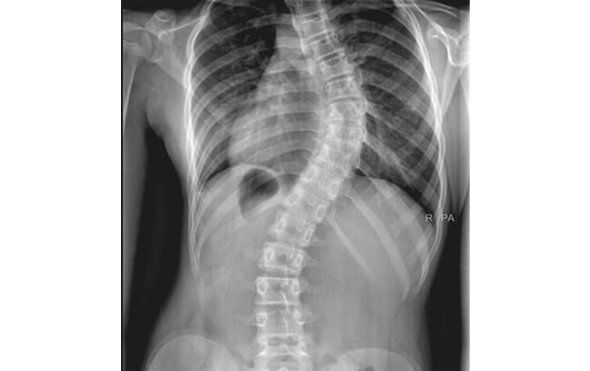

Omurgamızın yana eğilmeleriyle oluşan skolyoz, pek sık rastlanmasa da azımsanamayacak kadar mağduru olan bir omurga rahatsızlığıdır. Türkiye’de 2 milyonun üzerinde insanın sahip olduğu düşünülen bu rahatsızlığın genelde sebebi bilinmemekle beraber birkaç farklı nedeni bulunabilir.

Skolyoz doğuştan geliyor olabilir. Bu durumda gebelik döneminden kalan bir problem sonucu ortaya çıkar. Beyin felci sonucunda ya da kas ve sinir hastalıklarına bağlı da görülebilir. Genellikle normal gelişen bir omurgada, nedeni belli olmadan aniden baş gösterebilir. Bel ağrısı, sırttaki kozmetik kusurlar, gözle görülen bel eğiklikleri gibi belirtilerle kendisini gösterir

Skolyoz genelde ergenlik döneminde kendisini gösterse de çocuklar ve yetişkinlerde de bulunabilir. Ergenlik ve çocukluk dönemindeki skolyoz vakaları için, eğer eğrilik 20-25 ila 45 derece arasında ise skolyoz korse tedavisi tercih edilir. Skolyoz korse desteği yalnızca belirli eğrilik açıları için kullanılır. 45 dereceden fazla eğrilikler için genellikle ameliyat tedavisi uygulanır.

Skolyozun Dereceleri

Hafif skolyoz, omurlardaki eğriliğin 10 ila 20 derecenin arasında olduğu skolyoz tipidir. Genellikle tedavi gerektirmez ancak hasta olası bir ilerleme durumu için belirli aralıklarla muayene edilmelidir. Bu eğriliklerde skolyoza özgü egzersiler yapılabilir.

Orta derece skolyoz, eğriliğin 20 ila 45 derece arasında olduğu genelde çocuk ve ergenlerde kendisini hafif semptomlarla gösteren tiptir. Bu skolyoz tipinde cerrahi işlem tercih edilmez. Genelde iskelet gelişimi devam edene dek korse tedavisi uygulanır.

Şiddetli skolyoz, eğriliğin 45 derece ve üstü olduğu durumlarda kullanılan bir tabirdir.